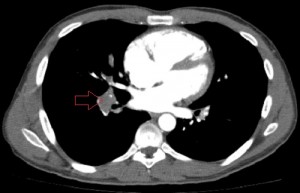

Axial images of CT angiogram of the pulmonary arteries 1 day after the patient’s admission showing filling defects in the central branches of both pulmonary arteries.